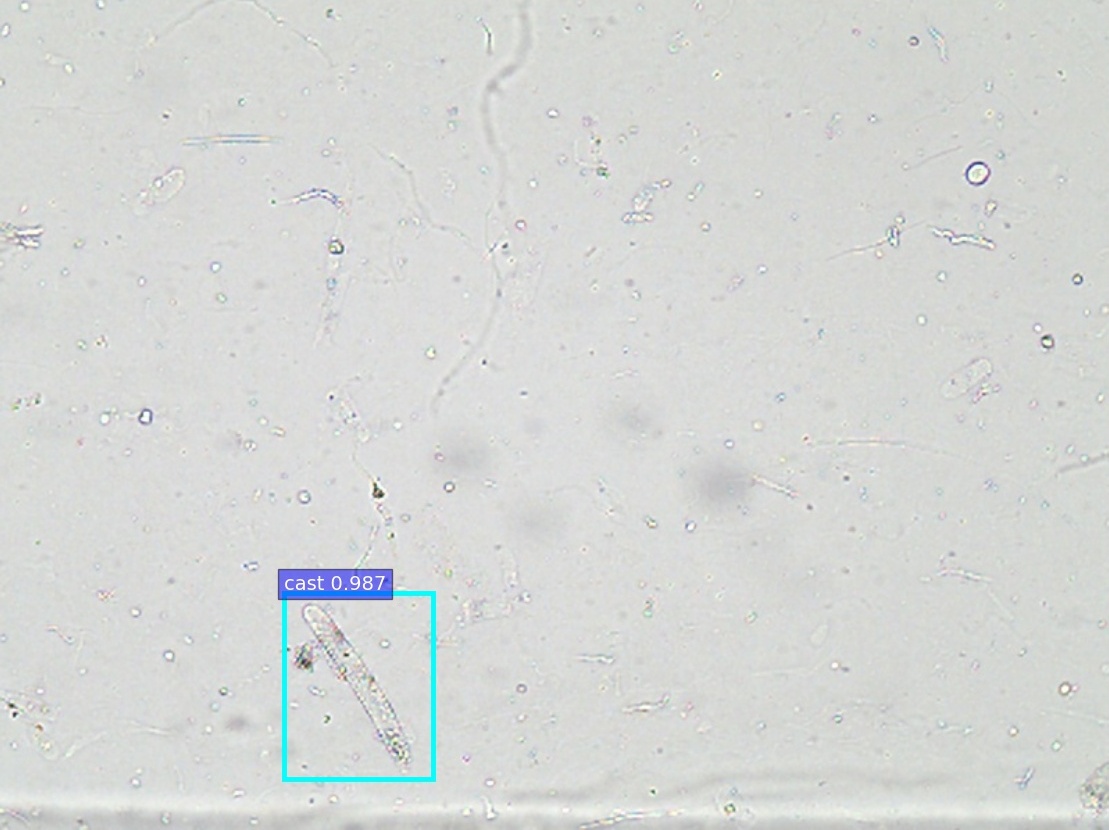

Refer to caption

(a) annotations

(b) ZF

(c) VGG-16

(d) ResNet-50

(e) PVANet

(f) SSD300

\Romannum7 : detection results of cast

Figure 8: Selected detection examples of urine particles on urinalysis test set. We show detections with scores higher than 0.7. All examples are divided into 7 groups, where 5 groups are at high-power field (i.e., erythrocyte, leukocyte, crystal, mycete, epithelial nuclei ) and the other 2 groups at low-power field (i.e., epithelial cell, cast ). In each group: (a) shows original image with ground truth boxes; (b-d) are Faster R-CNN detections separately on ZF, VGG-16 and ResNet-50 networks with a anchor scales of {322,642,1282,2562,5122}superscript322superscript642superscript1282superscript2562superscript5122\{32^{2},~{}64^{2},~{}128^{2},~{}256^{2},~{}512^{2}\}; (e) shows detection results on PVANet; (f) shows detection results on SSD300 model. For the ground truths and detection boxes, different categories use only different colors: eryth (red), leuko (black), epith (green), crystal (magenta), cast (cyan), mycete (yellow). As shown in this figure, the performance of SSD is inferior to Faster R-CNN, and it misses a lot of small objects.